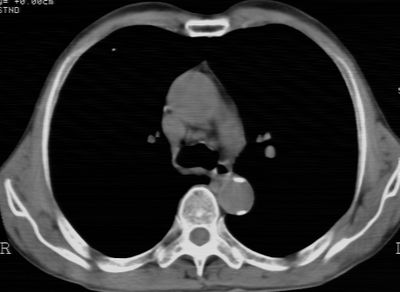

标题: CT24783:m71,既往肺心病史3年,现咳嗽,憋喘。 [打印本页]

标题: CT24783:m71,既往肺心病史3年,现咳嗽,憋喘。

1、左肺上叶spn,毛刺+分叶+血管集束征,考虑周围型肺癌可能性大

1)左肺上叶周围型肺癌可能。2)两肺全小叶型肺气肿。

左上周围型肺癌,全小叶型肺气肿。